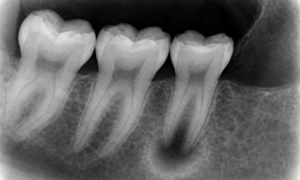

This is the small sensor placed inside your mouth. It captures the entire tooth from the crown to the root tip and the surrounding bone.

1. Purpose: To detect a specific Periapical Abscess Radiograph pattern at the root apex of a single tooth.

2. Technology: We use RVG (Radio Visio Graphy) sensors. These digital sensors provide instant high-resolution images on our computer screens with minimal radiation.

3. Best For Confirming cavities, root infections, and checking bone levels between teeth.

The most obvious sign of a Dentoalveolar Infection is a change in color at the tip of the tooth root.

1. Healthy Bone: Appears light grey or white because it is dense and mineralized.

2. Infected Bone: Appears as a dark spot or “halo” around the root tip. We call this Radiolucency.

This dark area exists because the bacterial toxins from the Teeth Abscesses have dissolved the calcium in the jawbone. The larger the dark spot, the more bone has been destroyed.

Before a massive hole appears in the bone, there are subtle signs that a Periapical Abscess Radiograph will reveal.

1. Widening of the PDL Space: The Periodontal Ligament (PDL) is a thin black line that surrounds the root. In early infection, this line becomes thicker as the ligament swells due to inflammation.

2. Loss of Lamina Dura: This is the thin white line of dense bone that lines the tooth socket. If this white line disappears or becomes fuzzy at the root tip, it confirms that the infection has breached the socket wall.